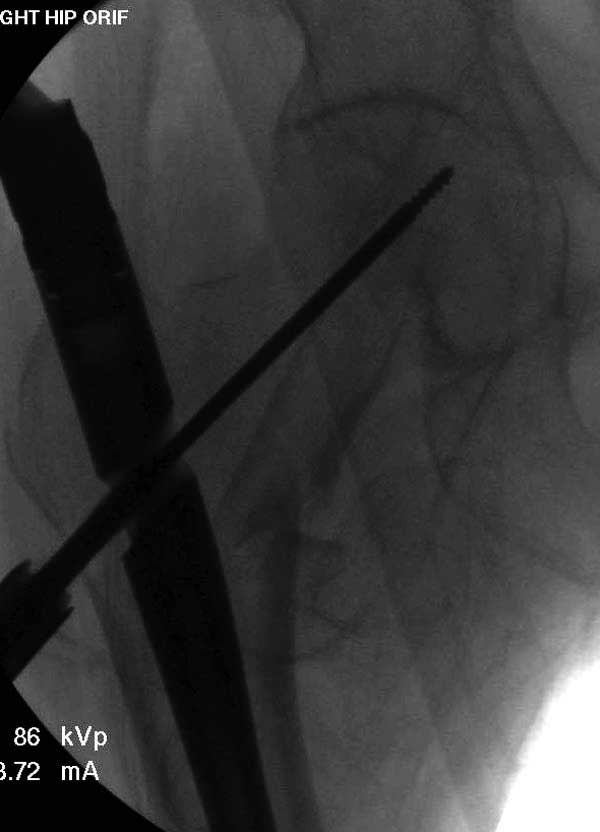

Прилагаю снимок сделанный еще в стационаре через 2 недели после операции.

Сеньоры-пэры ревизировали гвоздем, шуруп поставили по той же дорожке, только поглубже. Да еще и bone graft не пожалели. "Результат" уже был через 2 дня.

Первые снимки показывают технические погрешности установки DHS. Не была достигнута репозиция, конечность в флексии и шейка в ротации. Сегодня все меньше обращают внимание на параметры для оценки репозиции (S контуры Lowell в обеих проекциях и Garden Alignment Index, в норме 155 и 180 градусов), хотя такие простые тесты помогли бы дорепонировать смещение. Винт находится сзади в головке, что при нагрузке поменяет вектор и вместо компрессии в линии перелома срежет головку-Cut Out!

Вторая операция- это фаза сохранения головки бедра. Желательно приложить все усилия и сохранить головку, но, как видно, “фиаско” продолжается. Здесь вместо нейтрализации сил между медиальной и латеральными сторонами была попытка удержать варус. Варус не удержать ни деротационными шурупами о котором говорили и не костными стружками вбитые в шейку, потому что вся нагрузка упирается в головку.